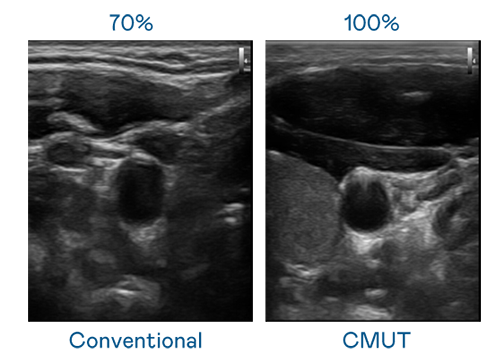

CMUT 技术是一种用电容式微机电元件来产生超音波讯号的技术。与传统 PZT 压电式技术相比,CMUT 频宽增加 30%,更宽频的超音波讯号让影像解析度大幅提升,是实现高影像品质医疗超音波扫描、促进精准医疗发展的关键技术。

大频宽带来超清晰影像

超音波影像的解析度高低,首先取决于探头能发出的讯号频宽。js3333线路检测中心(上海)有限公司 CMUT 可提供高清晰的超音波讯号,提供高频宽、高灵敏度、影像纹理细节更高的超音波影像,协助医护人员缩短影像判读时间及利用精准的医疗影像进行诊断。